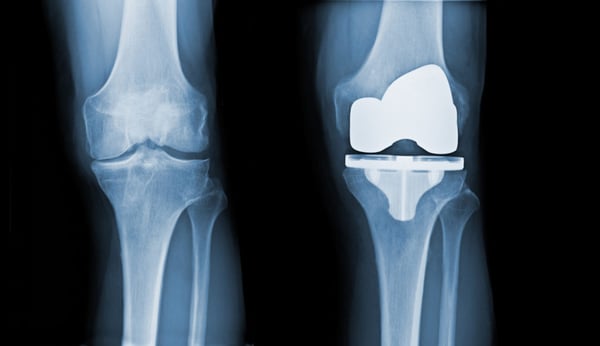

Total knee replacement (TKR) is a surgical procedure in which the damaged or worn-out surfaces of the knee are removed and replaced with components made of metal and plastic. These man-made components mimic the natural movement of a healthy knee, thereby relieving patients from pain, stiffness, and functional limitations.

- X-rays show bone-on-bone contact, indicating advanced joint degeneration.

- Removal of Damaged Surfaces: Using precise surgical tools, the surgeon cuts away the worn-out cartilage and bone from the femur (thigh bone), tibia (shin bone), and underside of the patella (kneecap). Special jigs and instruments help maintain correct alignment.

- Implantation of Prosthetic Components: The surgeon places metal caps on the femur and tibia, sometimes with bone cement. A plastic spacer is also inserted between them to allow smooth gliding. If needed, the back of the kneecap is also resurfaced with a plastic implant.